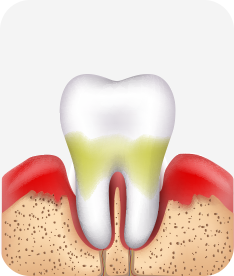

치주치료

청담네오플란트는 치주치료를 통하여 치아를 살릴 수 있는 기회를 놓치지 않습니다.

치주염(잇몸병)은 치아에 붙어있는 치석 및 세균 등에 의한 염증반응으로 잇몸뼈가 상실되는 질환을 말합니다.

초기에는 잇몸이 붓거나 잇몸에서 피가 나는 증상이 나타나며 계속 방치하면 치아를 발치해야 할 수도 있습니다.

치주치료는 이러한 치석 및 세균 등을 제거하여 잇몸뼈를 안정된 상태로 유지하는 시술을 말하며, 청담네오플란트에서는 치의학박사 / 전문의가 직접 시술하고 있습니다.

치주염 단계별 증상

건강한 상태

치아 주위의 잇몸이 핑크색을 띄며, 잇몸에서 피가 나지 않음.

스케일링을 6개월 ~ 1년 주기로 받고 올바른 칫솔질로 건강한 치주 조직을 유지

치은염 (초기~중기)

치아 주위의 잇몸이 붉게 부어 있으며, 칫솔질 등을 할 때 피가 남.

스케일링 주기의 조절이 필요할 수 있으며, 올바른 칫솔질을 시행하여야 함.

치주염 (중기~말기)

주기적으로 잇몸이 붓고 피가 나며, 욱씬하거나 우리한 통증이 나타남.

치주치료 및 정도에 따라 치주수술(잇몸수술)이 필요함. 향후 관리 정도에 따라 3~6개월 간격으로 내원하여 유지치료를 시행하여야 함.

치주염 (말기)

잇몸이 항상 부어 있으며, 이가

흔들리는 정도가 점점 심해짐.

치주치료가 필요하며, 정도에 따라 치아를 발치하여야 할 수 있음.